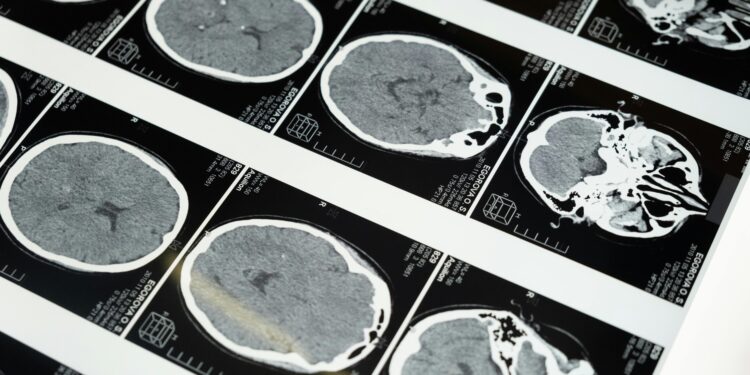

A infecção teve início com sintomas pulmonares e evoluiu até problemas neurológicos, levando médicos a uma biópsia cerebral que resultou na descoberta do parasita.

Durante meses, médicos trataram a paciente para uma pneumonia eosinofílica, já que seus exames de sangue mostravam níveis elevados de eosinófilos, indicadores de infecção parasitária. Contudo, sem sucesso, uma piora nos sintomas neurológicos, como perda de memória, levou a nova investigação.

A remoção do parasita exigiu um procedimento cirúrgico delicado e após a cirurgia, a paciente iniciou tratamento antiparasitário para garantir que não restassem larvas no organismo.